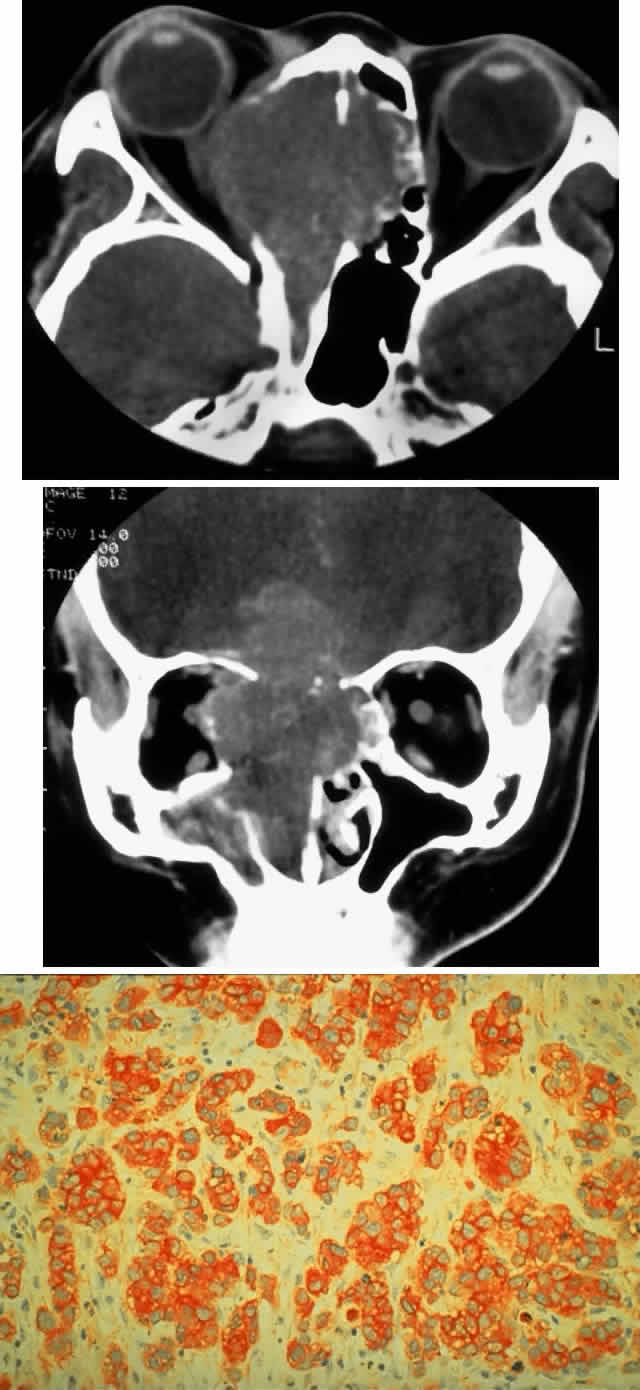

Radiologic findings consist of either focal or widespread destruction of the sinuses, with invasion of the adjacent structures by a solid tumor mass (Fig. 2). The mass is usually large; however, sometimes it may be relatively small but may extend to adjacent structures, particularly in the case of adenoid cystic carcinoma (Fig. 3). The sinus and orbit may be the only structures involved, but there is frequently extension to the base of the skull.

Fig. 2. A 32-year-old woman presented with a 1-month history of sinus congestion and nasal obstruction unresponsive to antibiotics. In the 1 week preceding the initial exam, the right eye became progressively more prominent and showed tearing and redness. On examination, there was mild edema of the lower lid and dysesthesia in the distribution of cranial nerve V2, and the globe was displaced 6 mm laterally and 5 mm anteriorly. There was mild limitation of abduction, chemosis, and nasal choroidal folds. An axial CT scan revealed a diffuse, destructive soft tissue mass centered in the superior nasal passage and ethmoid sinuses extending into the right orbit in contiguity with the medial rectus (A). On enhanced coronal view, the tumor was noted to involve the right maxillary antrum and to extend superiorly into the anterior cranial fossa (B). Biopsy of the sinus (C) revealed an alveolar-type rhabdomyosarcoma (muscle stain, × 320).